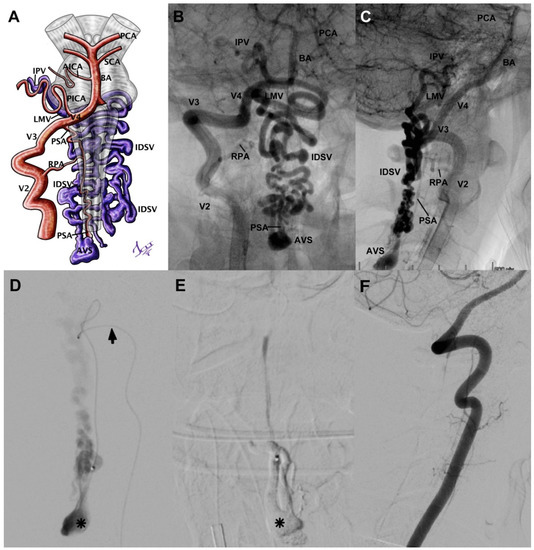

3.5.4. Case 10

| Case 10 | 18/M | Lumbar pain, acute myelopathy, paraparesis (2/5), headache, vomiting, and SAH at cranial base and perimedullary | 4 | Conus medullaris compact AVM (Spetzler) | Radiculomedullary arteries at left D11 and L1 | Compact nidus from D12 to L2 | No | Toward varicose perimedullary vein–lumbar segmentary vein | Embolized with Histoacryl in 2 sessions | Complete occlusion without sequel | 0 |